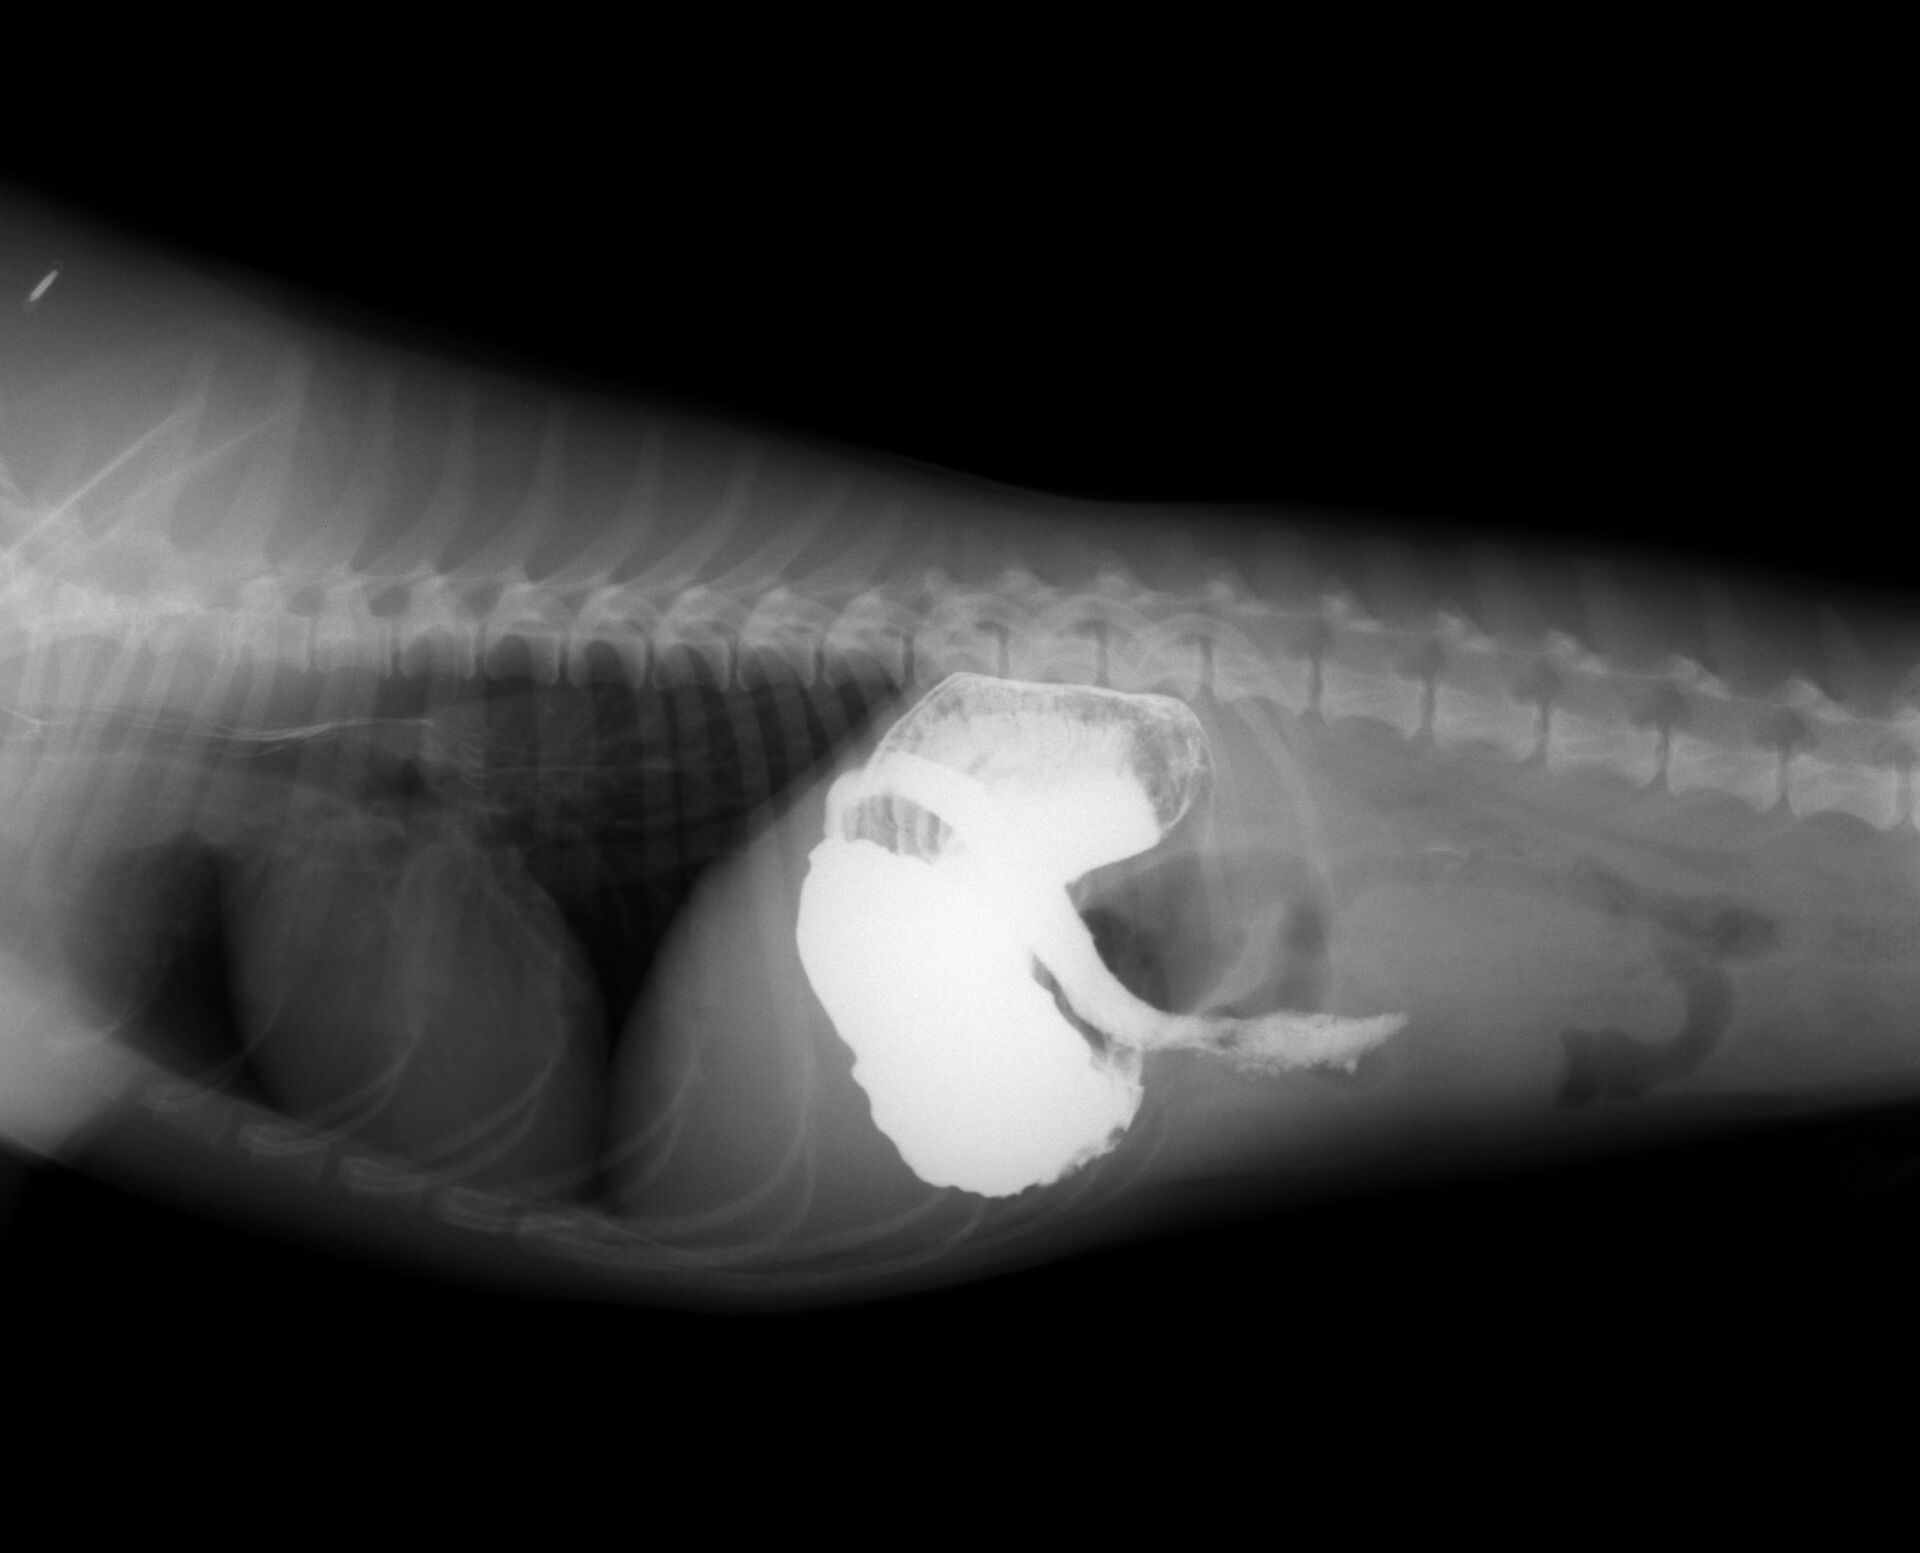

バリウム投与後15分です。

バリウム投与後30分です。